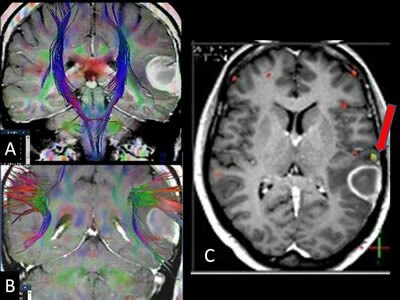

• La tractografía por tensor de difusión (DTI)

La tractografía por tensor de difusión (DTI)

Es un sistema de planificación prequirúrgica y de guía intraoperatoria sirve como la eliminación de lesiones cerebrales en el interior o adyacente a áreas que tienen riesgo de ser lastimadas las fibras subcorticales que nacen de ellas.